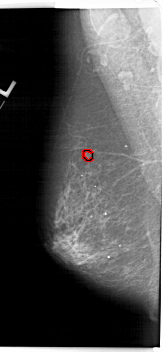

FILE: A_1165_1.LEFT_MLO.OVERLAY

TOTAL_ABNORMALITIES 1

ABNORMALITY 1

LESION_TYPE MASS SHAPE OVAL MARGINS ILL_DEFINED

ASSESSMENT 4

SUBTLETY 2

PATHOLOGY MALIGNANT

TOTAL_OUTLINES 1

BOUNDARY